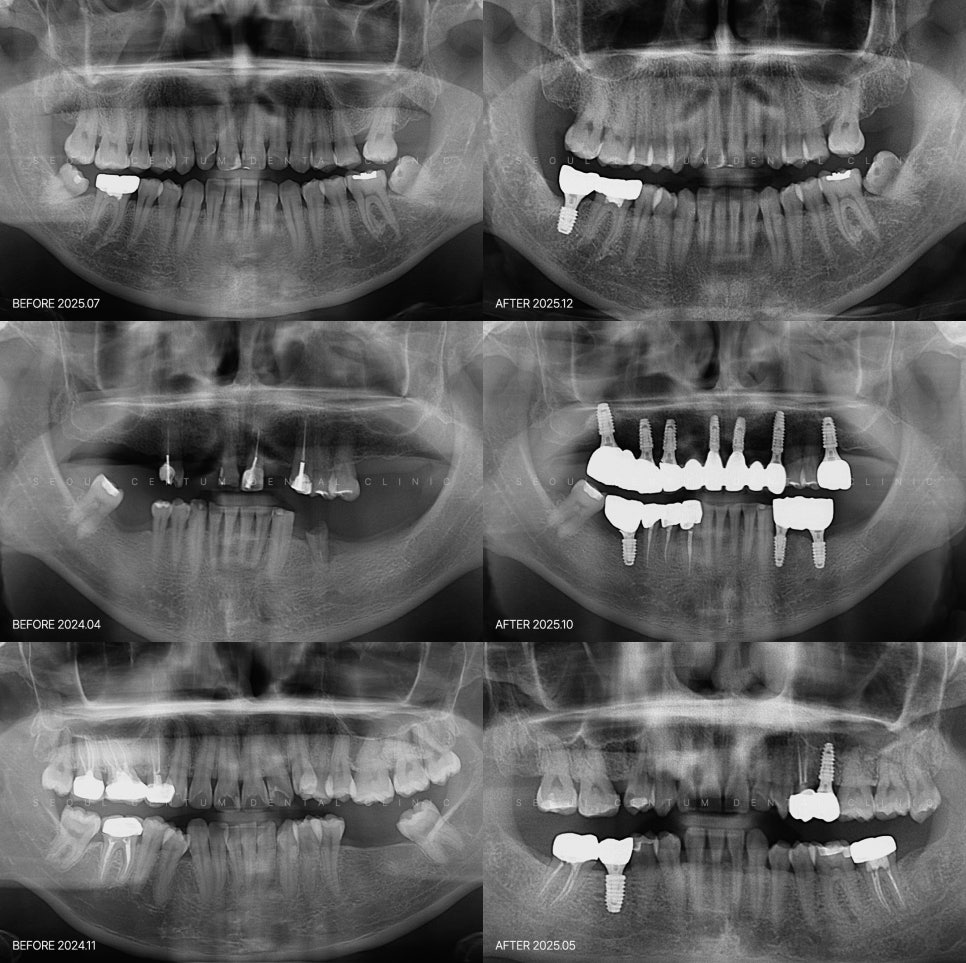

서울센텀치과의원 신사역의 네이버 블로그 원문을 보존한 아카이브 페이지입니다. 임플란트 카테고리의 발치 후에 들어가는 임플란트 시기 어떤 기준으로 결정이? 글을 통해 병원의 한국어 정보 제공 방식과 진료 관련 안내 톤을 확인할 수 있습니다.

자연치가 있던 자리의 공백을 어떻게 채울지 고민이 필요합니다. 갖가지 이유로 치아 상태가 많이 좋지 않으면 발치를 하는 편이 나은데요. 그 이후 빈 공간을 복구하는 건 구강 건강을 유지하는 데 꼭 필요합니다~ 내버려두면 잇몸뼈 흡수나 교합 불균형 등이 진행될 수 있거든요. 이 때문에 발치 후 임플란트 시기를 앞...